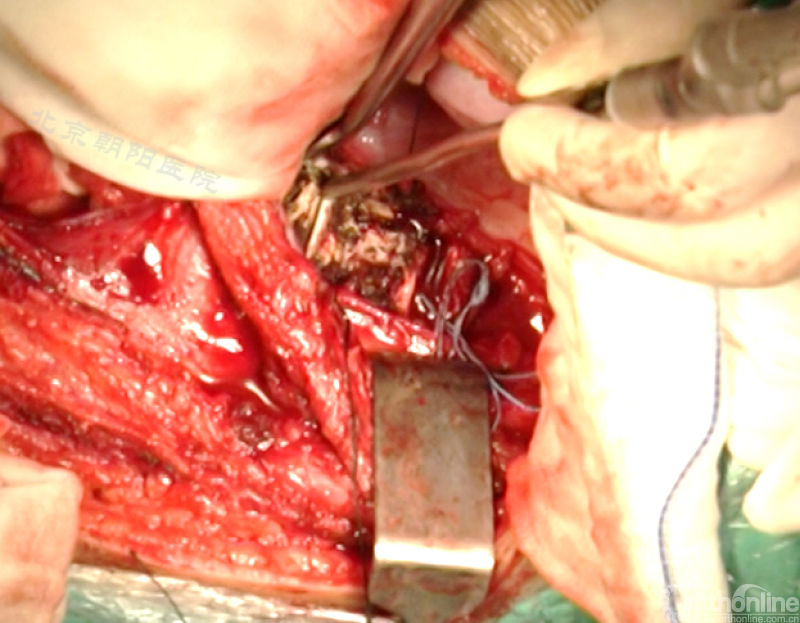

患者11岁青少年女性,诊断为Lenke 5C型AIS,T10-L4 Cobb角50.5°、T5-10 Cobb角31.5°,主弯顶椎为L1,融合范围选择为T1-L3。

术者:首都医科大学附属北京朝阳医院骨科 海涌教授

经近端需内固定的椎体(T11)相对应的肋骨表面做一弧形切口,分离浅层软组织直至肋骨表面的多层肌肉组织,切口止于脐的远端偏外侧。

骨膜下环形剥离完整显露肋骨。

切开第11肋骨肋软骨的连接部,并将肋骨靠近脊柱的部位切断。

同理将第12肋骨摘除。

由第12肋前端软骨部位进入腹膜后间隙,可以见腹膜后脂肪。

经腹壁和横膈下方钝性分离腹膜内组织。

切开横膈进入胸腔侧,术中由双肺呼吸改为凹侧单肺呼吸。

沿脊柱表面纵行切开腹膜,显露腹腔侧,注意避免伤及节段性血管。

在术中神经检测下逐个结扎切断节段动脉,术中注意监测脊髓供血情况。

切开纤维环,去除终板椎间盘组织,直至纤维环的后侧边缘,对于严重侧凸如果需要可至后纵韧带。

进一步使用刮匙和髓核钳完整去除椎间盘组织和终板,营造植骨面。

内固定选择的是5.5mm双棒系统,先置入顶椎的螺钉垫板。

置入顶椎的椎体螺钉,螺钉可置入椎体中部到后方1/3之间的范围内。

使用双棒系统时,先置入背侧的螺钉,螺钉指向椎体中线,后置入腹侧的螺钉,螺钉轻度指向后侧。形成对椎体的三角形抓持力。

胸腔侧、腹腔侧螺钉全部置入后,骨移植物植人的越靠近后纵韧带或者纤维环的后缘越好。

将预先折弯的金属棒先置入背侧。

椎间融合器经前方置入凹侧,确保腰椎前凸的恢复和冠状面畸形的矫正,将剩下的骨移植物置入椎间隙内。

置入腹侧金属棒。

使用双棒系统时先安装背侧的棒,可进行90°的去旋转,也可以直接通过前方螺钉矫正冠状面和矢状面的畸形,然后固定后方的棒,可进一步通过加压矫正冠状面畸形。

矫正后神经检测未见异常术中唤醒患者下肢活动良好,术中透视矫正效果满意、内固定位置良好。根据手术具体情况放置合适尺寸的横连接加强内固定。

尽量多的闭合胸膜,紧密缝合横膈。

分别缝合第11、12肋骨的骨膜。

留置合适直径的胸腔闭式引流管,根据术中情况选择是否放入腹腔引流。逐层缝合腹壁,逐层缝合皮下组织和皮肤。